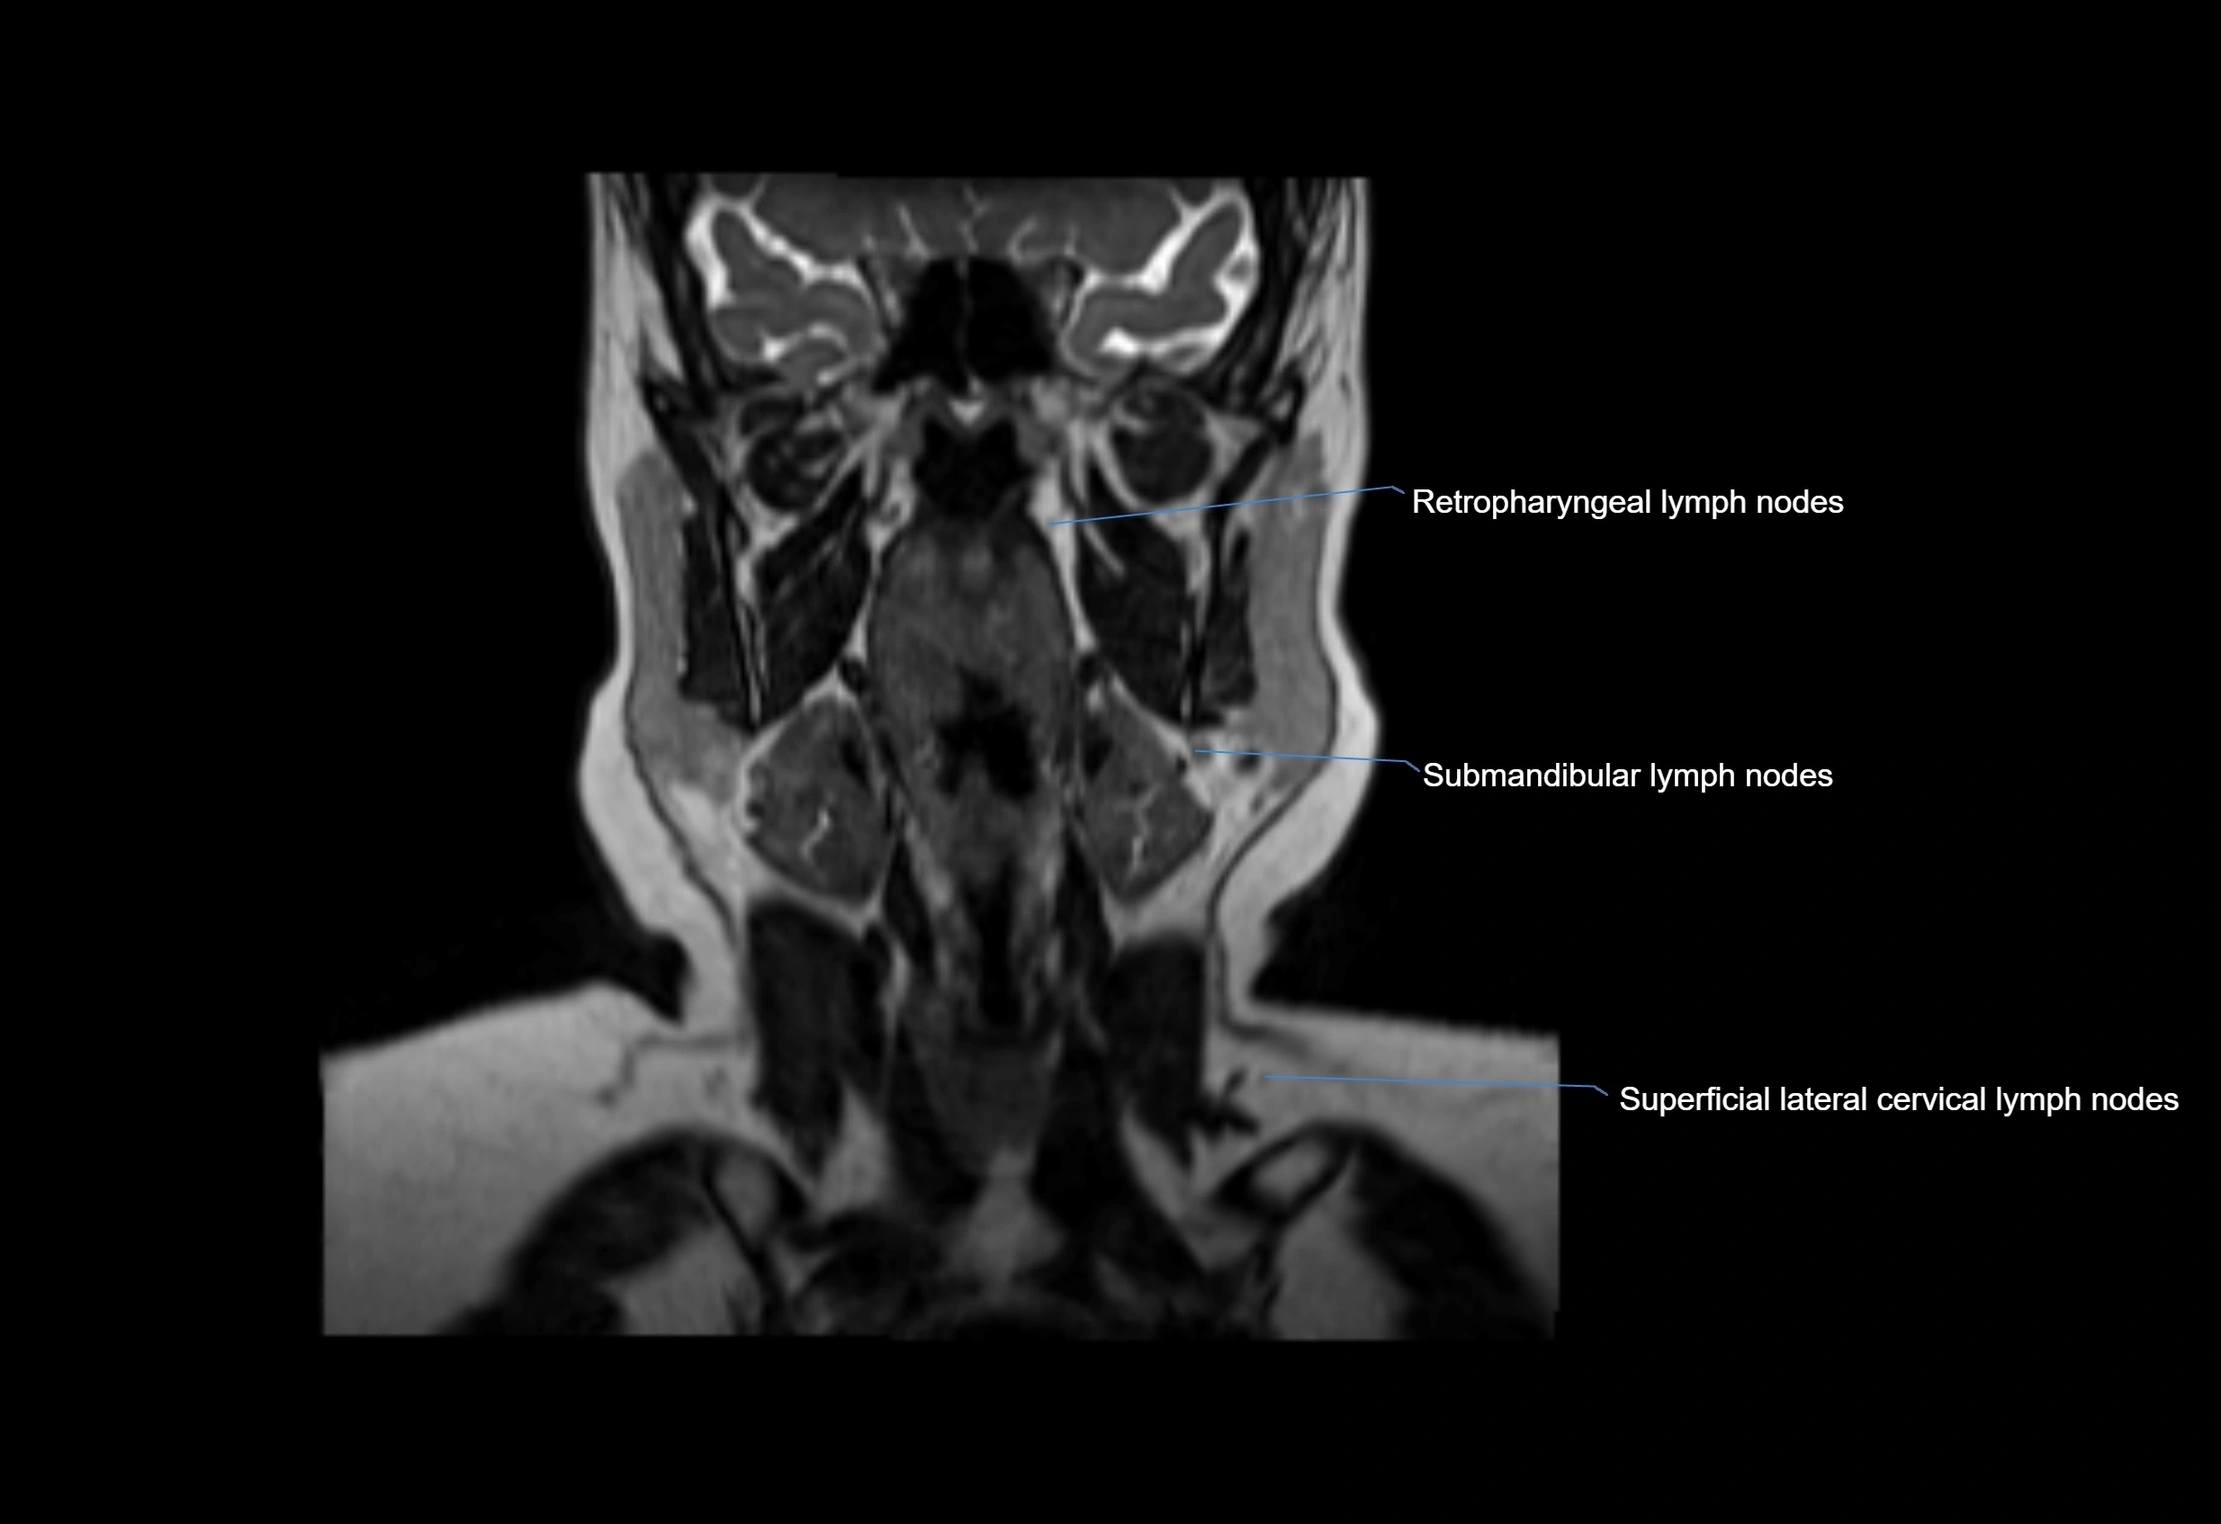

MRI Appearance

T1-weighted images:

• Normal accessory nodes appear as small, oval hypointense to intermediate signal structures within subcutaneous fat

• Surrounded by hyperintense fat, enhancing contrast for visualization

• Pathological nodes may appear enlarged or rounded, sometimes with cortical thickening

T2-weighted images:

• Nodes show intermediate signal, with surrounding fat bright

• Useful for detecting edema, inflammation, or infiltration

• Fatty hilum may appear slightly hyperintense relative to cortex

MRI images

image